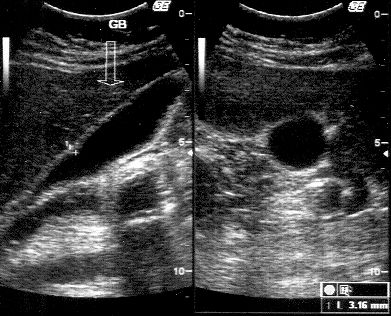

Histologic examination showed a gallbladder wall with moderate chronic inflammatory infiltrate and foamy macrophages in lamina propria. There was thickening of the muscularis. There were no features suggestive of malignancy in the processed section. Rokitansky Aschoff sinuses are seen (Figure 3). The final diagnosis of the strawberry gallbladder was made.

Figure 3 Microscopic examination of the gallbladder specimen.